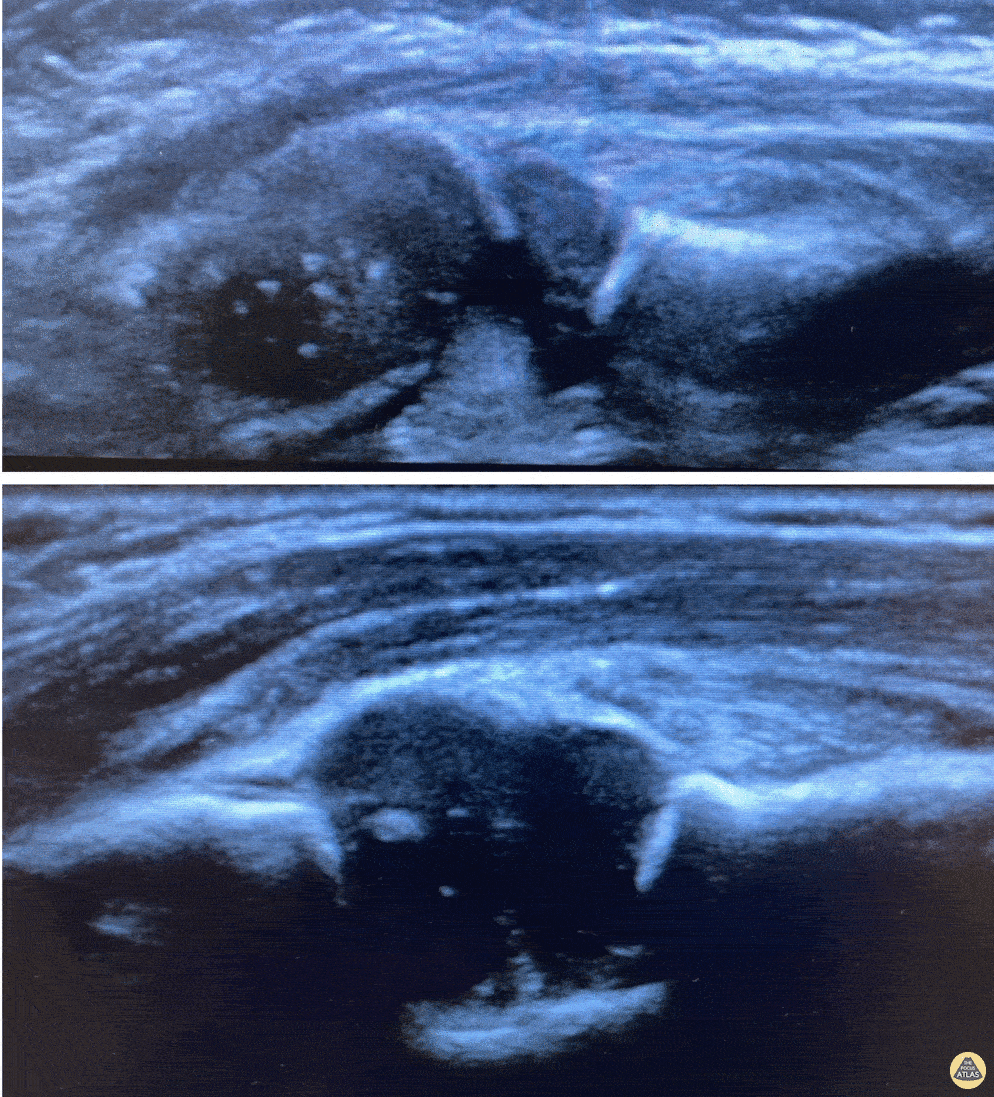

Nursemaid's pre and post reduction. Nathan Jia, Orthopedic Resident